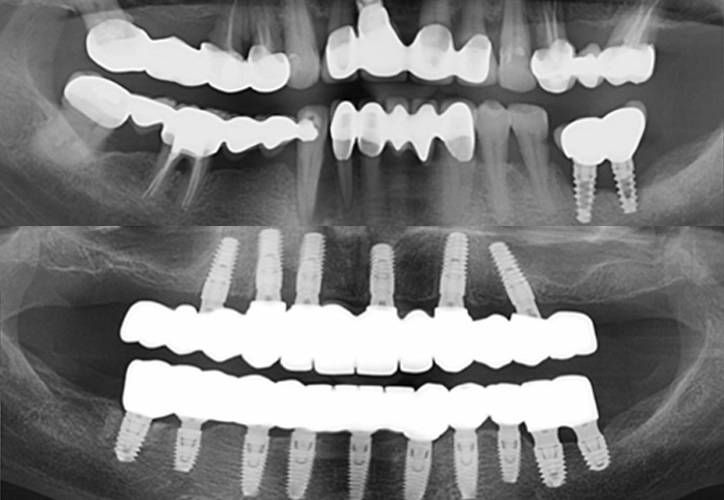

Extractia tuturor dinților naturali;

Explantația implanturilor vechi;

Inserarea de implanturi noi;

Lucrări protetice implanto-purtate din oxid de zirconiu